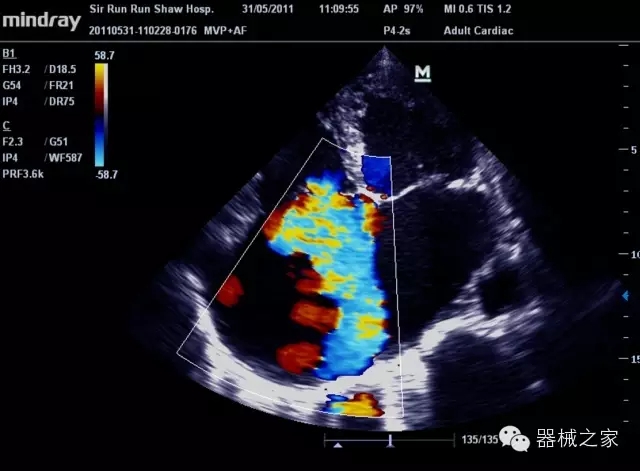

臨床圖片賞析

產(chǎn)品特點(diǎn)

·在便攜式緊湊平臺(tái)上采用更多倍波束并行接收信號(hào)處理模式,無論二維還是彩色血流圖像狀態(tài)下,擁有更靈敏的回波頻移捕獲能力,大大提高時(shí)間分辨率,尤其使得心血管表現(xiàn)更為突出;